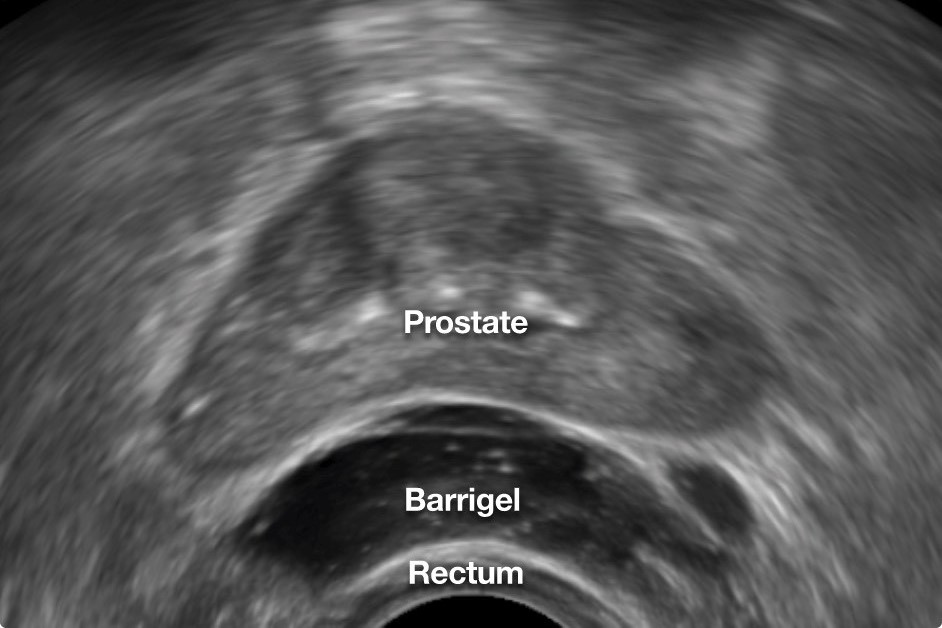

Rectal spacer improves prostate radiation side effects

June 10, 2025

Cancer Care